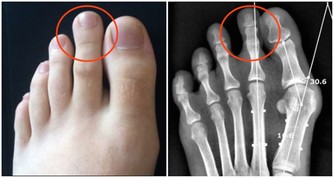

(3) 壓迫症狀,當腫瘤向周圍組織浸潤或壓迫神經時,可引起腹痛、腰痛或坐骨神經痛,若壓迫盆腔靜脈,可出現下肢浮腫;巨大的腫瘤可壓迫膀胱,有尿頻、排尿難、尿瀦留;壓迫直腸則大便困難;壓迫胃腸道便有消化道症狀;壓迫膈肌可發生呼吸困難,不能平臥。

(5)疼痛,因癌腫轉移而出現相應的症狀,卵巢惡性腫瘤極少引起疼痛,如發生腫瘤破裂、出血或感染或由於浸潤壓迫鄰近臟器可引起腹痛、腰痛。